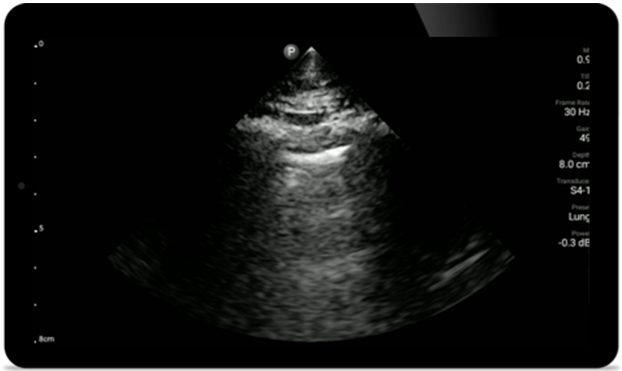

Use Lumify for airway and pulmonary assessment

Lumify POCUS solutions can help you detect the endotracheal tube within the trachea, assist in emergent cricothyrotomy procedures, diagnose pleural effusion and interstitial alveolar diseases.

• High-resolution imaging for abdominal and cardiac applications: Cardiac, OB/GYN, Lung, Abdomen and FAST imaging preset optimizations